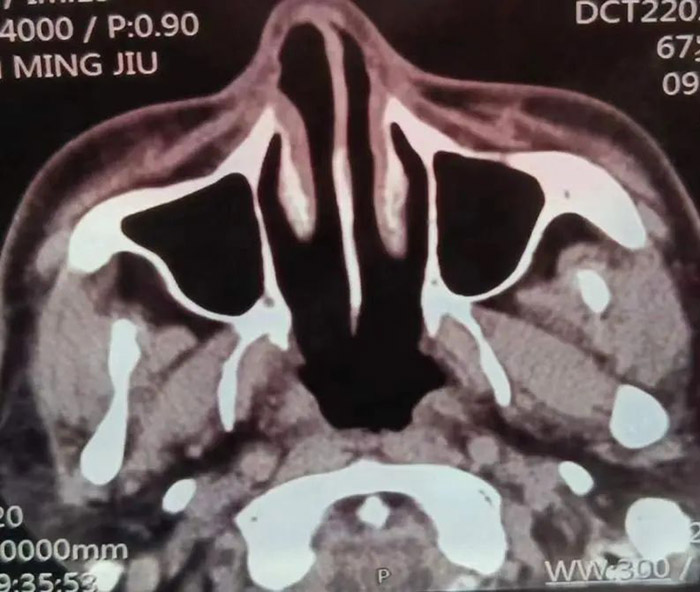

罹患肿瘤 初战告捷 68岁的范先生,于2014年1月27日因鼻腔流血、鼻塞、鼻腔分泌物有异味等症状,来到我院耳鼻喉科就诊。经鼻咽部CT扫描,发现鼻咽占位。在完成肿瘤部分摘除术后,转入我院放疗科,进一步做鼻咽癌放疗根治术。

经过一个疗程的放射治疗后,范先生的病情达到了临床预期的效果,原有症状明显改善或消失,一个月后CT复查效果提示,鼻咽癌残余肿瘤放疗后明显缩小,病情稳定好转 。

2021年7月,这是患病的第七年,范先生发现自己的右眼逐渐视物不清,原以为只是年龄的问题老花眼或眼疲劳。但是从眼球逐渐外凸后,他开始紧张起来。在家人的陪伴下,范先生来到我院检查病情。鼻咽部CT显示:鼻咽癌复发,PET/CT结果显示:筛窦蝶窦有浸润、鼻腔转移、眼球外凸系肿瘤变大外张导致。

经过专家组研究,制定了二次放疗的方案,并对放射治疗过程进行分期评估和监控,以便进行方案修改与调整。这次治疗采用了先进的TaiChiPro双模式放射治疗系统。随着治疗次数的增加,范先生明显感觉自己的症状逐渐减轻。接近一个疗程的时候,他的视力已经恢复了很多,眼球外凸也明显回缩,除味觉稍差,其它的症状都没有出现。出院后一个月复查,CT提示鼻咽癌及转移灶明显改善,眼球外凸症状消失。

二次放疗后的CT图像和右眼恢复情况